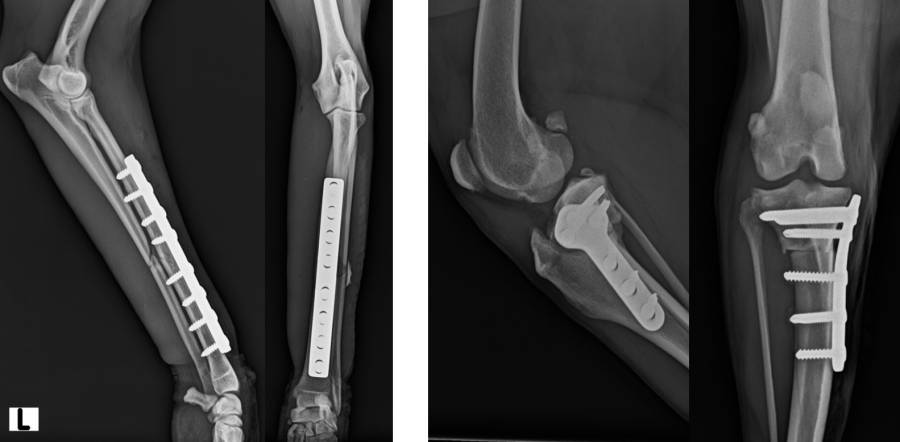

Röntgen post OP mit Implantaten